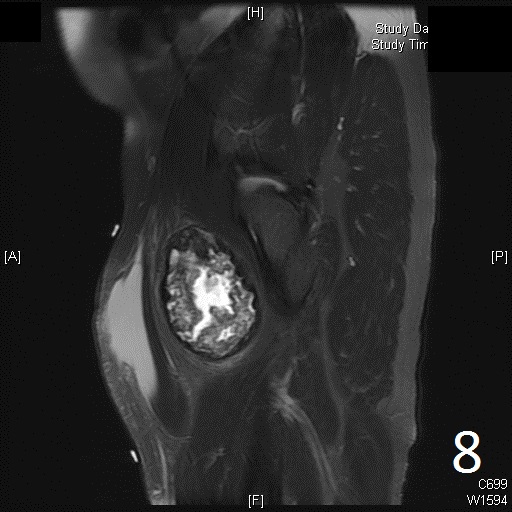

• Well defined heterogenous mass on T2W (Fig. 4, 9)

• Necrosis and hemorrhage are common, especially in high grade tumors

Fig. 5-9: Axial and sagittal (Fig. 6) MRI shows a fibrosarcoma in the proximal quadriceps muscle that is isointense to muscle on T1W images, and a heterogeneous on T2W FS (Fig. 7, 8). The patient was treated with preoperative chemotherapy and the mass underwent extensive necrosis. The mass does not show any enhancement with contrast due to the extensive necrosis. There is only peripheral enhancement with contrast on T1W FS (Fig. 9).